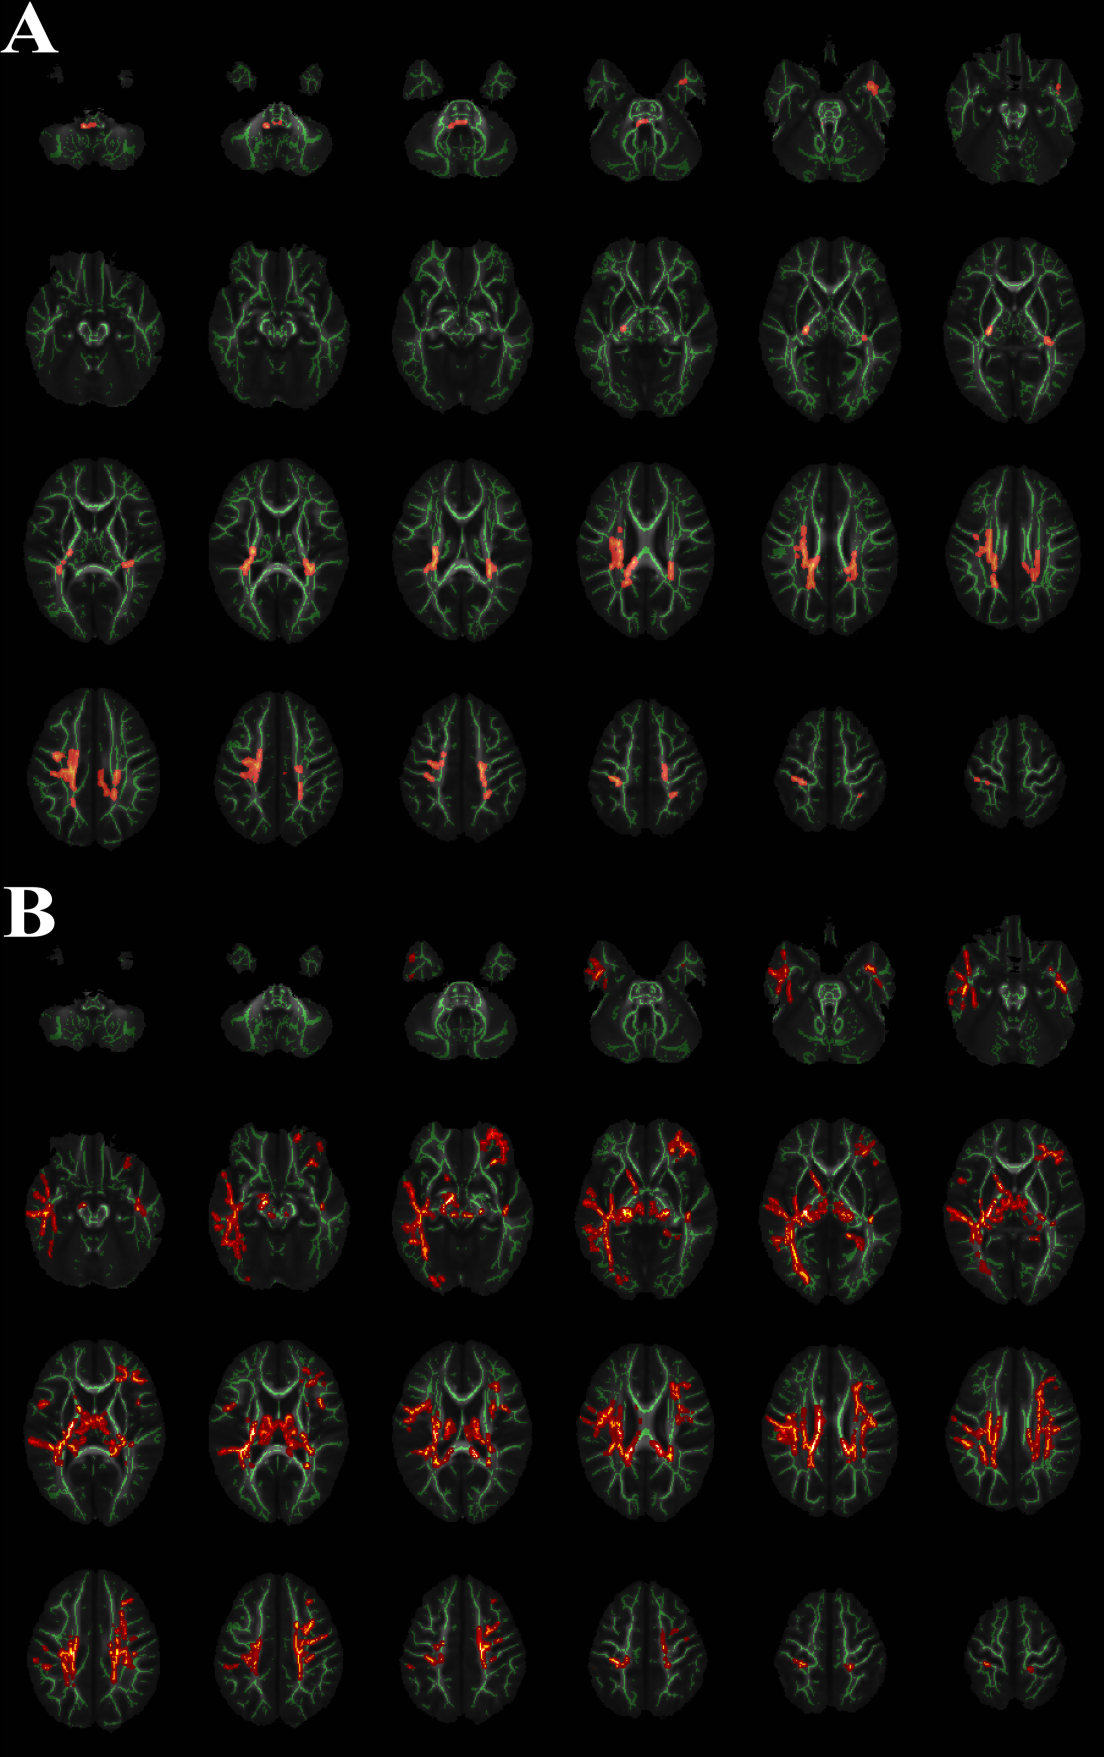

Figure 1.White Matter regions with significant increasing FA and AD values in IGHD group versus the TD group

Areas in red are regions where FA (Panel A) and AD (Panel B) were significantly higher (P<0.05, corrected by TFCE) in IGHD group relative to TD group. To aid visualization, regions showing increased FA/AD (red) are thickened using the tbss_fill script implemented in FSL. The left side of the image corresponds to the right hemisphere of the brain.

*IGHD = Idiopathic growth hormone deficiency; TD = typically developing; FA = Fractional Anisotropy; AD = Axial Diffusivity

In the TBSS analysis, the IGHD group showed increased fractional anisotropy (FA) values (mainly in bilateral posterior corona radiata) and increased axial diffusivity (AD) values (mainly in 3 fibers: right retrolenticular part of internal capsule and bilateral posterior corona radiata) (P < 0.05, TFCE corrected) (Table 1, Fig. 1). However, there were no significant differences in RD and MD values. Total score of CBCL were positively associated with FA values in the cluster of left posterior corona radiata (r=0.351 P=0.014) (Fig. 2).